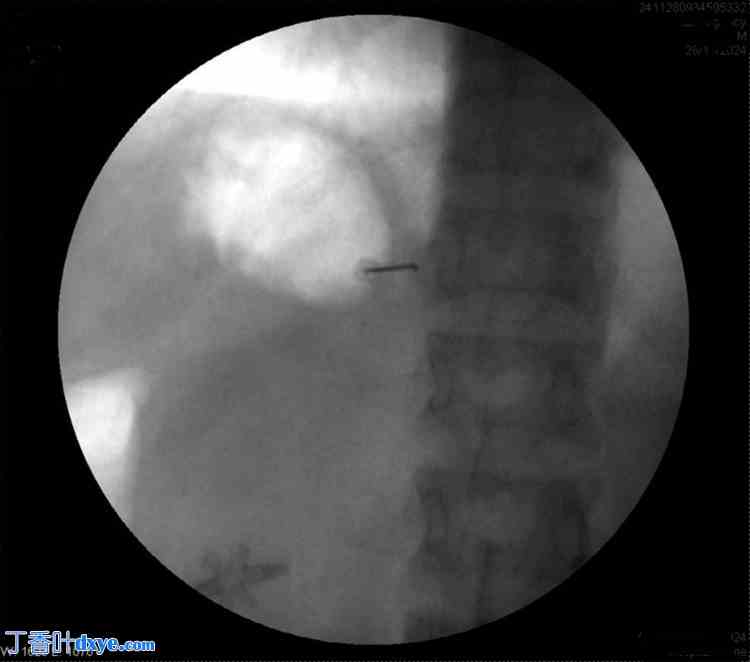

患者取俯卧位。涂抹并铺巾后,在C臂辅助下将T8横突定位于右侧。在透视引导下插入Quincke针(22 G),到达T8横突。针尖沿横突向尾部推进,直至感觉无阻力。在透视下注射碘海醇300放射性造影剂确认针头位置,并拍摄前后位和侧位图像(图1-4)。

图 4. 放射造影剂注射后的侧位荧光透视图。